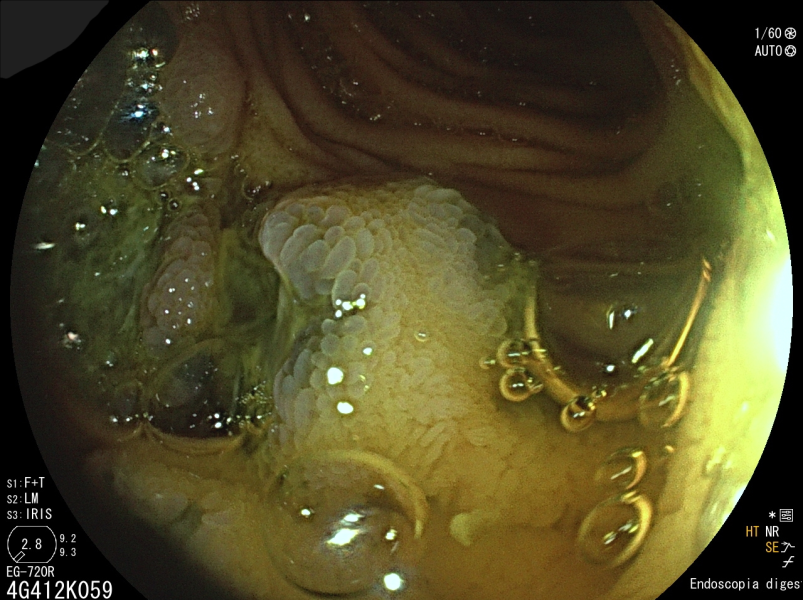

Swiss Cheese Esophagus

Fotografia